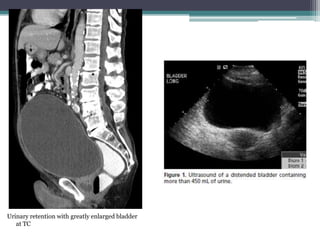

Urinary retention with greatly enlarged bladder

at TC